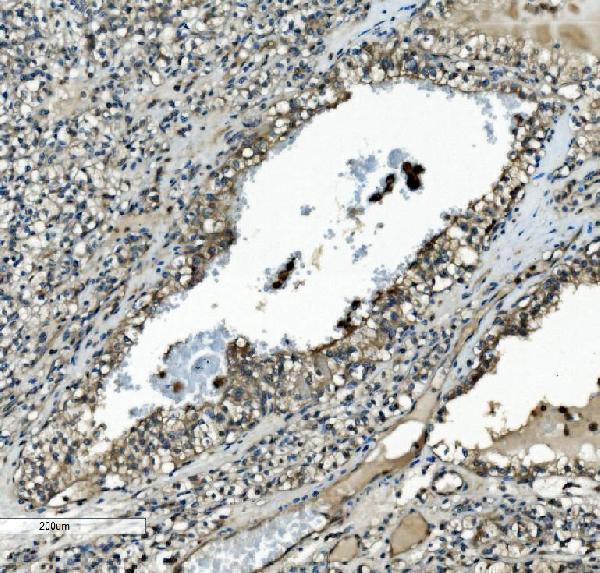

Facts about Dual specificity mitogen-activated protein kinase kinase 2.

| Gene Name: | MAP2K2 |

Cytoplasm. Membrane; Peripheral membrane protein. Membrane localization is probably regulated by its interaction with KSR1.